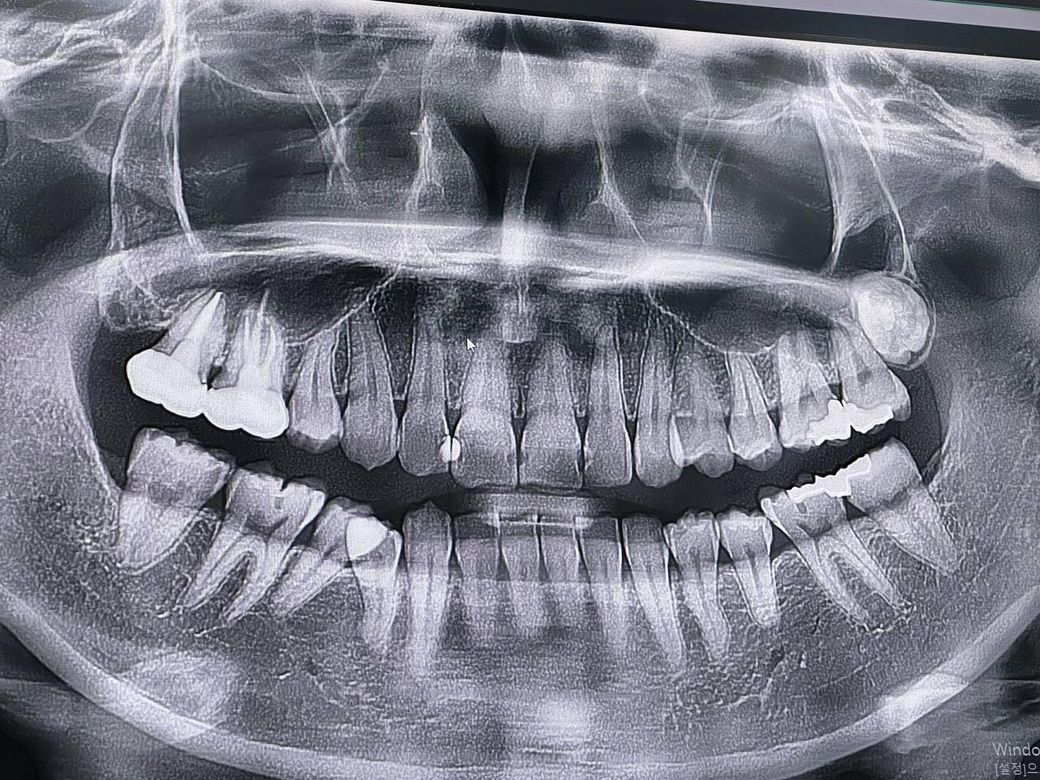

어금니쪽 크라운치료 필요여부에 대해 문의드립니다

인접면에 충치있다고 해서 치료 받았는데 크라운으로 하는게 맞나요?

사진상으로 왼쪽 아해 부분 크라운과

오른쪽 뒤에서 두번째 치아와 위쪽 치아 크라운 치료를 하는 게 맞는지 확인하고 싶습니다

어금니쪽은 치간 사이를 인레인으로 하기 어려운가요?

• 1번 째 사진

사진으로 봤을 경우 인접면에 충치가 있는것으로 보입니다 인접면의 충치가 크게 생겼을 경우에는 크라운 치료를 하는것이 좋습니다.

1. 치근단 사진 없이 파노라마 사진가지고 인접면 충치에 대한 진단을 정확히 하는 것은 무리가 있고요.

2. 질문자분이 생각하시는 것처럼, 굳이 인레이가 되는데 크라운을 하는 것은 아닌가?에 대한 판단 역시 치과의사마다 각각의 판단기준이 있기 때문에 뭐라 조언하기가 어렵네요.

3. 일반적으로, 3면이상의 인레이를 하는 경우(MOD인레이 등..)는 예후가 불량하여 금방 망가지거나, 치아에도 안좋을 수 있어서 크라운이나 온레이를 하자고 권합니다.

4. 어금니 치간 사이 인레이라고 언급주신 부분은 2급 인레이(옆면+씹는면)인데, 인레이 주된 치료가 그거입니다. 지금도 사진상 왼쪽 위, 아래 2급 인레이를 하신거고요